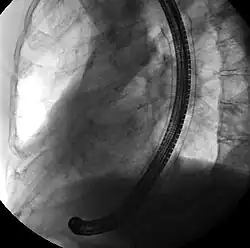

![]() Endoscopic view of a self-expandable metallic stent used to palliate an esophageal cancer | |

A self-expandable metallic stent (or SEMS) is a metallic tube, or stent that holds open a structure in the gastrointestinal tract to allow the passage of food, chyme, stool, or other secretions related to digestion. Surgeons insert SEMS by endoscopy, inserting a fibre optic camera—either through the mouth or colon—to reach an area of narrowing. As such, it is termed an endoprosthesis. SEMS can also be inserted using fluoroscopy where the surgeon uses an X-ray image to guide insertion, or as an adjunct to endoscopy.